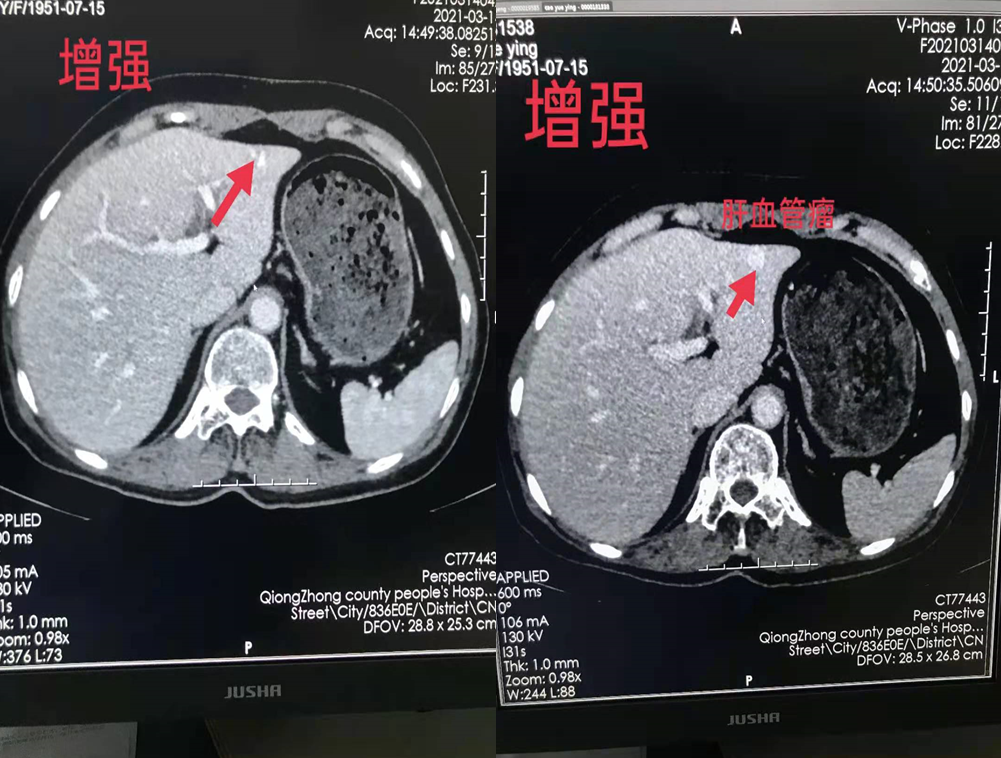

四、开展项目:科室现常规开展全身各部位CT平扫及增强检查、CT三维重建、CT血管造影(CTA、CTV)、(包括冠状动脉CTA)、CT尿路造影(CTU)、全身各部位DR摄片检查、床边摄片、同时开展胆系T管造影、CT定位下穿刺活检。

常规CT增强检查